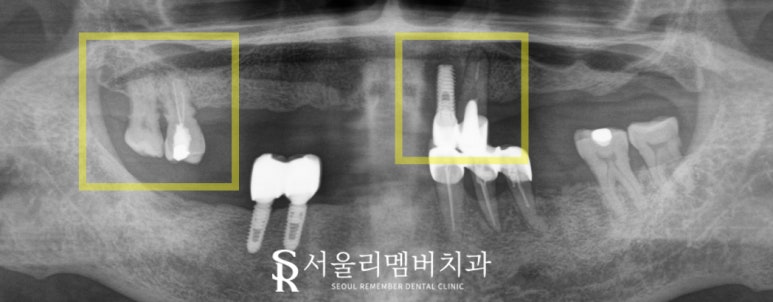

초진 사진을 보면

몇 개의 자연치들이 구강 내에 남아있었는데요.

과연 이곳들을 살릴 수 있을지에 따라

어떤 보철을 사용할지 결정이 되겠네요.

제대로 확인하기 위해 엑스레이를 촬영했습니다.

상악에 있는 잔존치들은 살릴 수 없을 정도로

염증이 심해져 있었으며 치조골도 좋지 않았는데요.

상악 잔존치들은 다 뽑는 것이

구강 건강에 있어 더 좋은 방법이라는 판단이 들었습니다.

하악도 상태가 그리 좋은 편은 아니었으나

다행히 치료가 시급할 정도로 급한 곳들은 없었습니다.